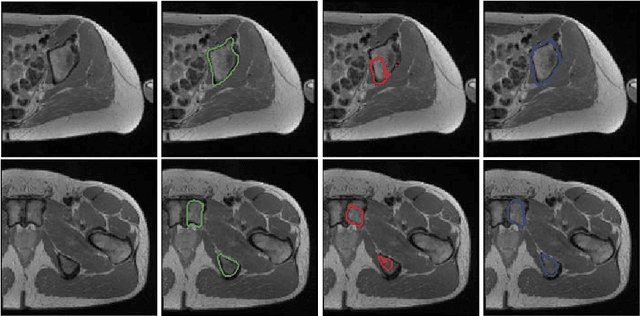

Abstract:We propose a 2D Encoder-Decoder based deep learning architecture for semantic segmentation, that incorporates anatomical priors by imitating the encoder component of an autoencoder in latent space. The autoencoder is additionally enhanced by means of hierarchical features, extracted by an U-Net module. Our suggested architecture is trained in an end-to-end manner and is evaluated on the example of pelvic bone segmentation in MRI. A comparison to the standard U-Net architecture shows promising improvements.